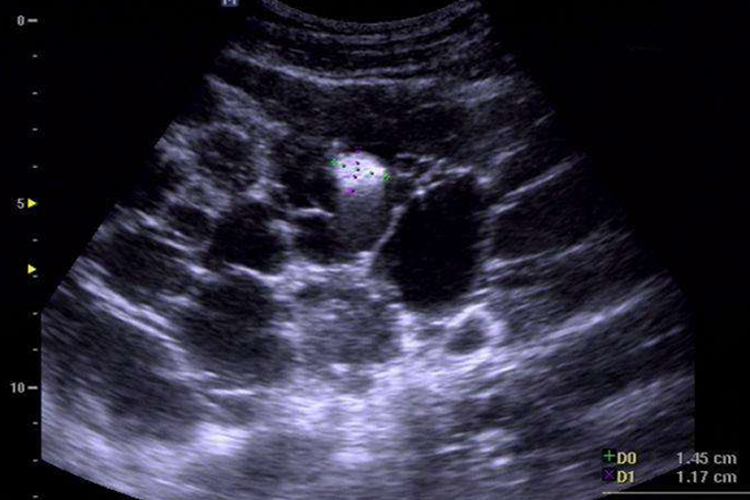

超声表现为双肾显著增大,表面不规则,肾皮质、髓质内许多大小不等囊泡样无回声和低回声结构,囊壁清晰、整齐。肾窦区被多数囊泡压迫变形,甚至显示不清。